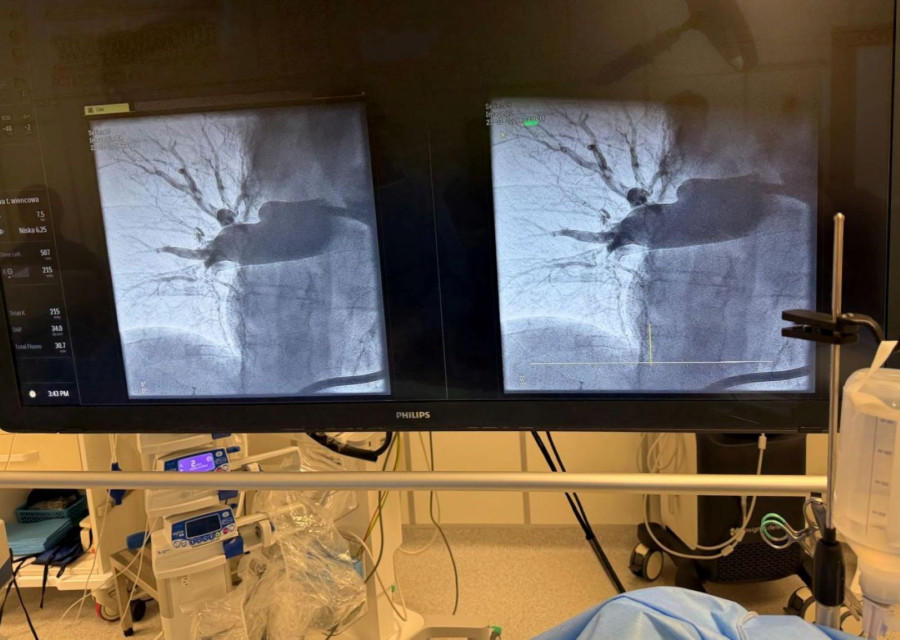

Pacjent został pilnie przekazany do Kliniki Kardiologii, gdzie lekarze zdecydowali o natychmiastowym leczeniu zabiegowym. W pracowni Radiologii Zabiegowej wykonano trombektomię płucną z użyciem systemu Penumbra, polegającą na mechanicznym usunięciu skrzeplin z tętnic płucnych.

Masywna zatorowość płucna to stan bezpośrednio zagrażający życiu, wymagający natychmiastowych i zdecydowanych działań. W tym przypadku, wobec nieskuteczności leczenia zachowawczego, zdecydowaliśmy się na wykonanie trombektomii płucnej z wykorzystaniem systemu Penumbra. To małoinwazyjna metoda, która pozwala na szybkie usunięcie materiału zatorowego i natychmiastową poprawę parametrów krążeniowo-oddechowych – podkreśla dr hab. n. med. Piotr Rola, profesor Politechniki Wrocławskiej, kierownik Kliniki Kardiologii.